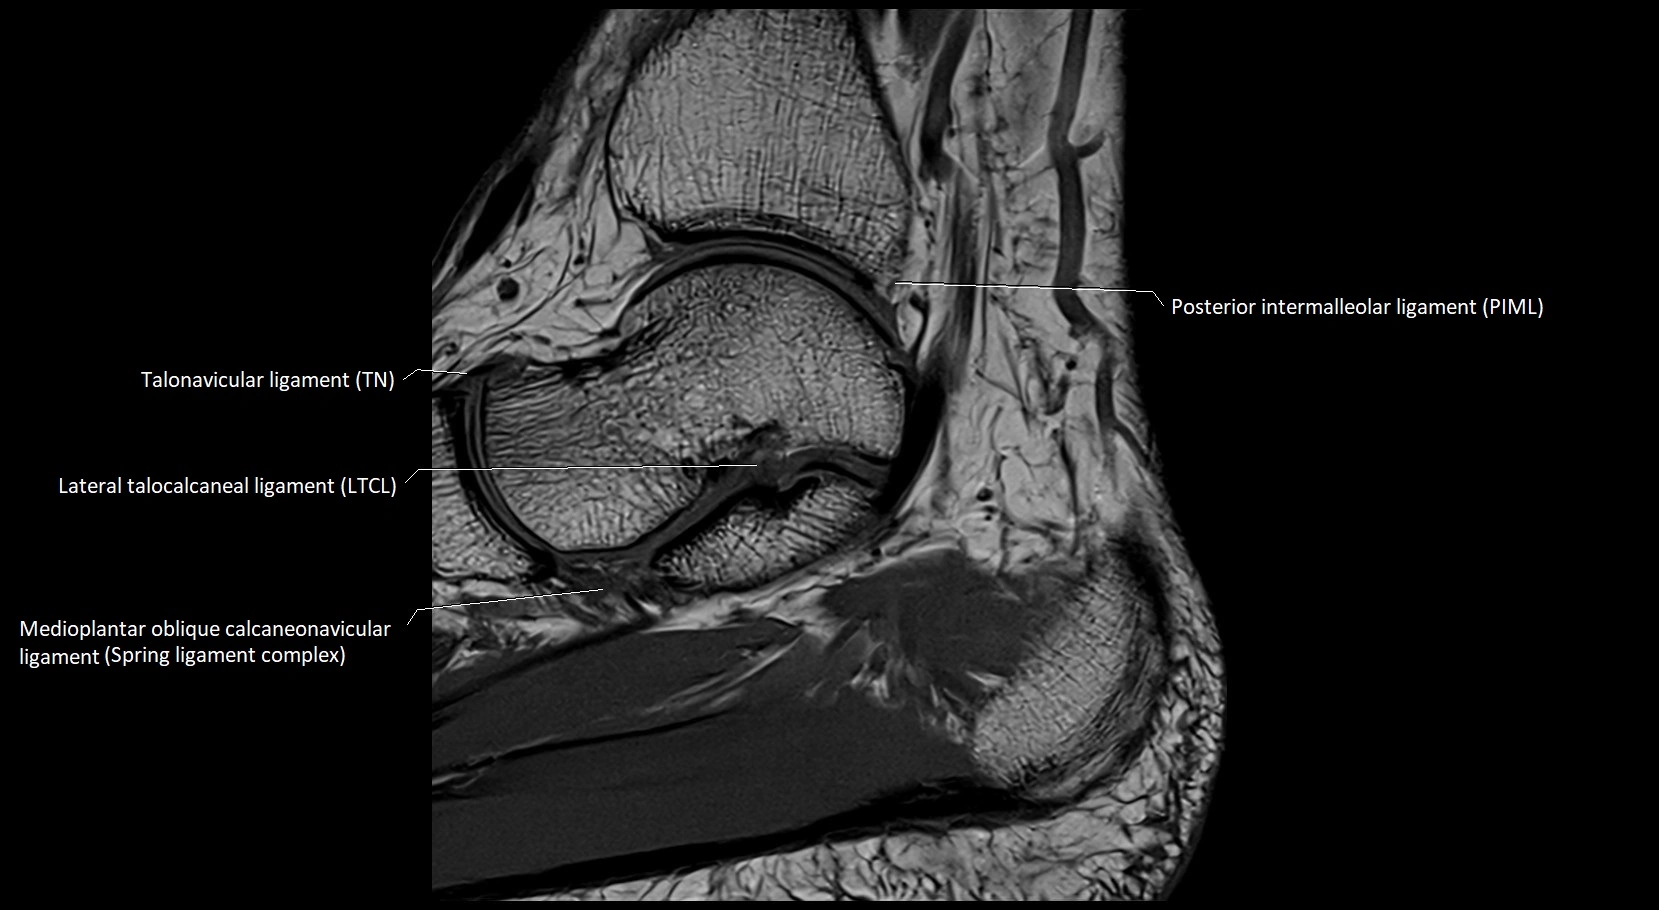

MRI image

image